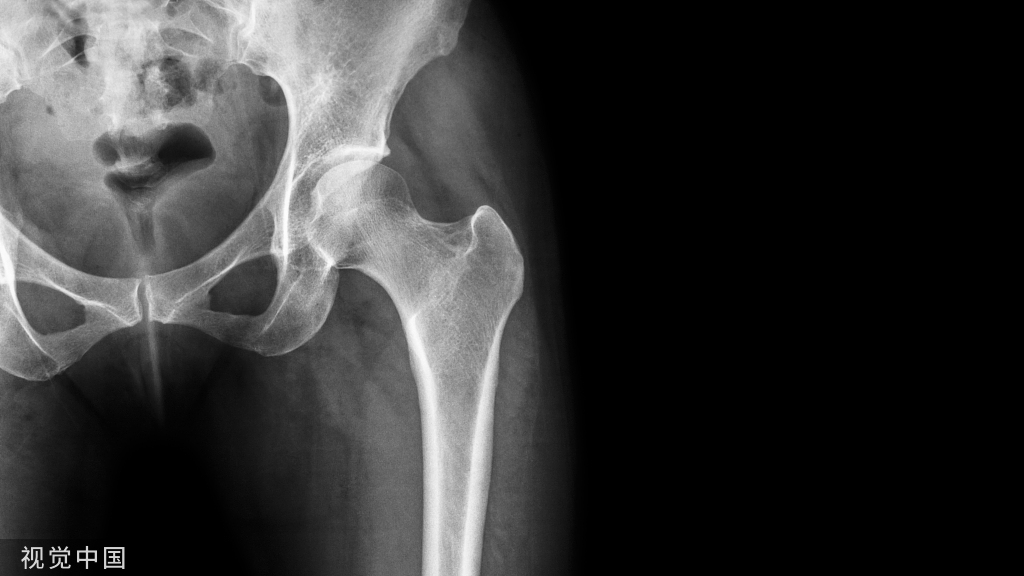

X线检查,确认骨折愈合